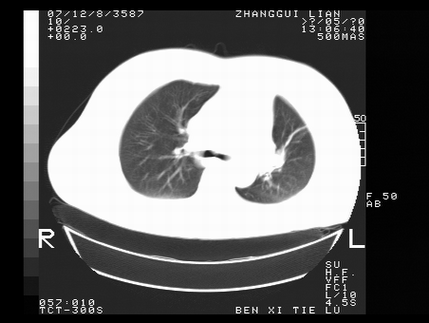

标题: CT10818:男,73,TB病史,现病史肺炎及直肠CANCER术后 [打印本页]

标题: CT10818:男,73,TB病史,现病史肺炎及直肠CANCER术后

这个请版主删除掉,这个病例我发过的,发重了,此人病史是,f,46y,胸疼,无其他原因就诊

左侧中央型肺癌伴阻塞性肺炎\\不张,左侧前上纵隔亦增宽,建议上传纵隔窗除外淋巴结转移.

考虑:左侧中央型肺癌伴阻塞性肺炎,纵隔淋巴结转移。

1)考虑为:左侧中央型肺癌伴阻塞性肺炎,纵隔淋巴结转移。2)双侧少量胸腔积液。3)心包积液。

左侧中央型肺癌伴阻塞性肺炎,纵隔淋巴结转移。

考虑左侧中央型肺癌伴阻塞性肺炎,纵隔淋巴结转移。